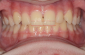

No casos de Clase III